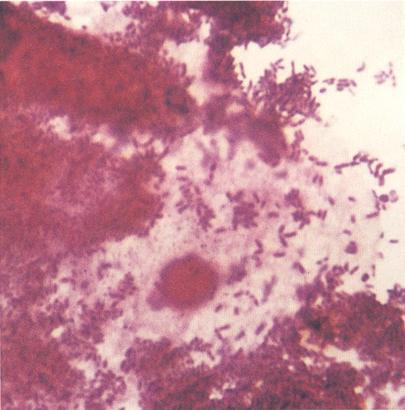

Fig. 21.5.5.3: Frotiu sugestiv pentru vaginoza bacteriana: (coloratie Gram, x1000, imagine din colectia proprie a laboratorului)